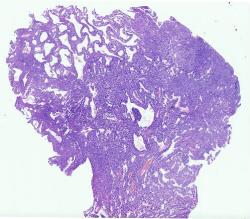

10536 |

男, 36岁, 【主诉】发现纵隔肿物3天

【现病史】患者 2024-07-... |

上海交通大学附属仁济医院 |

有诊断 |